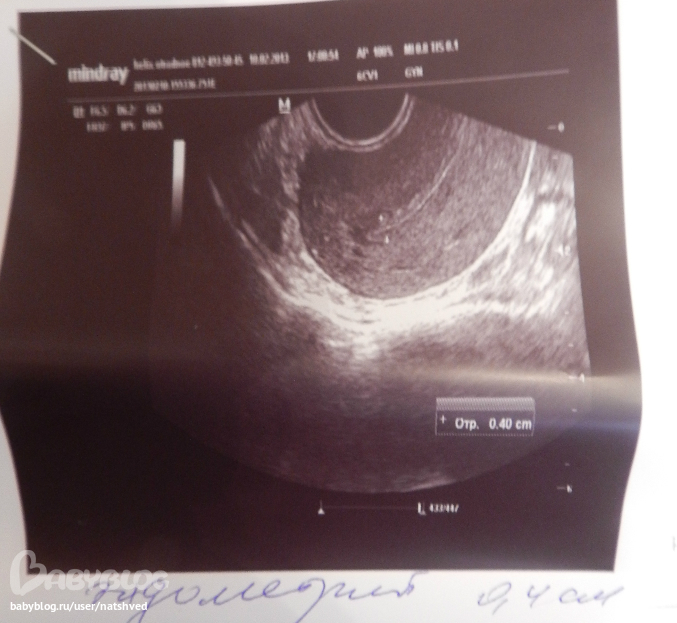

эндик 4мм